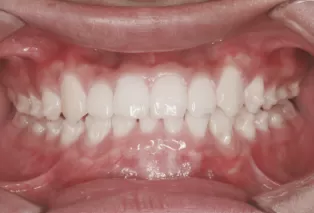

Photos intra-orales